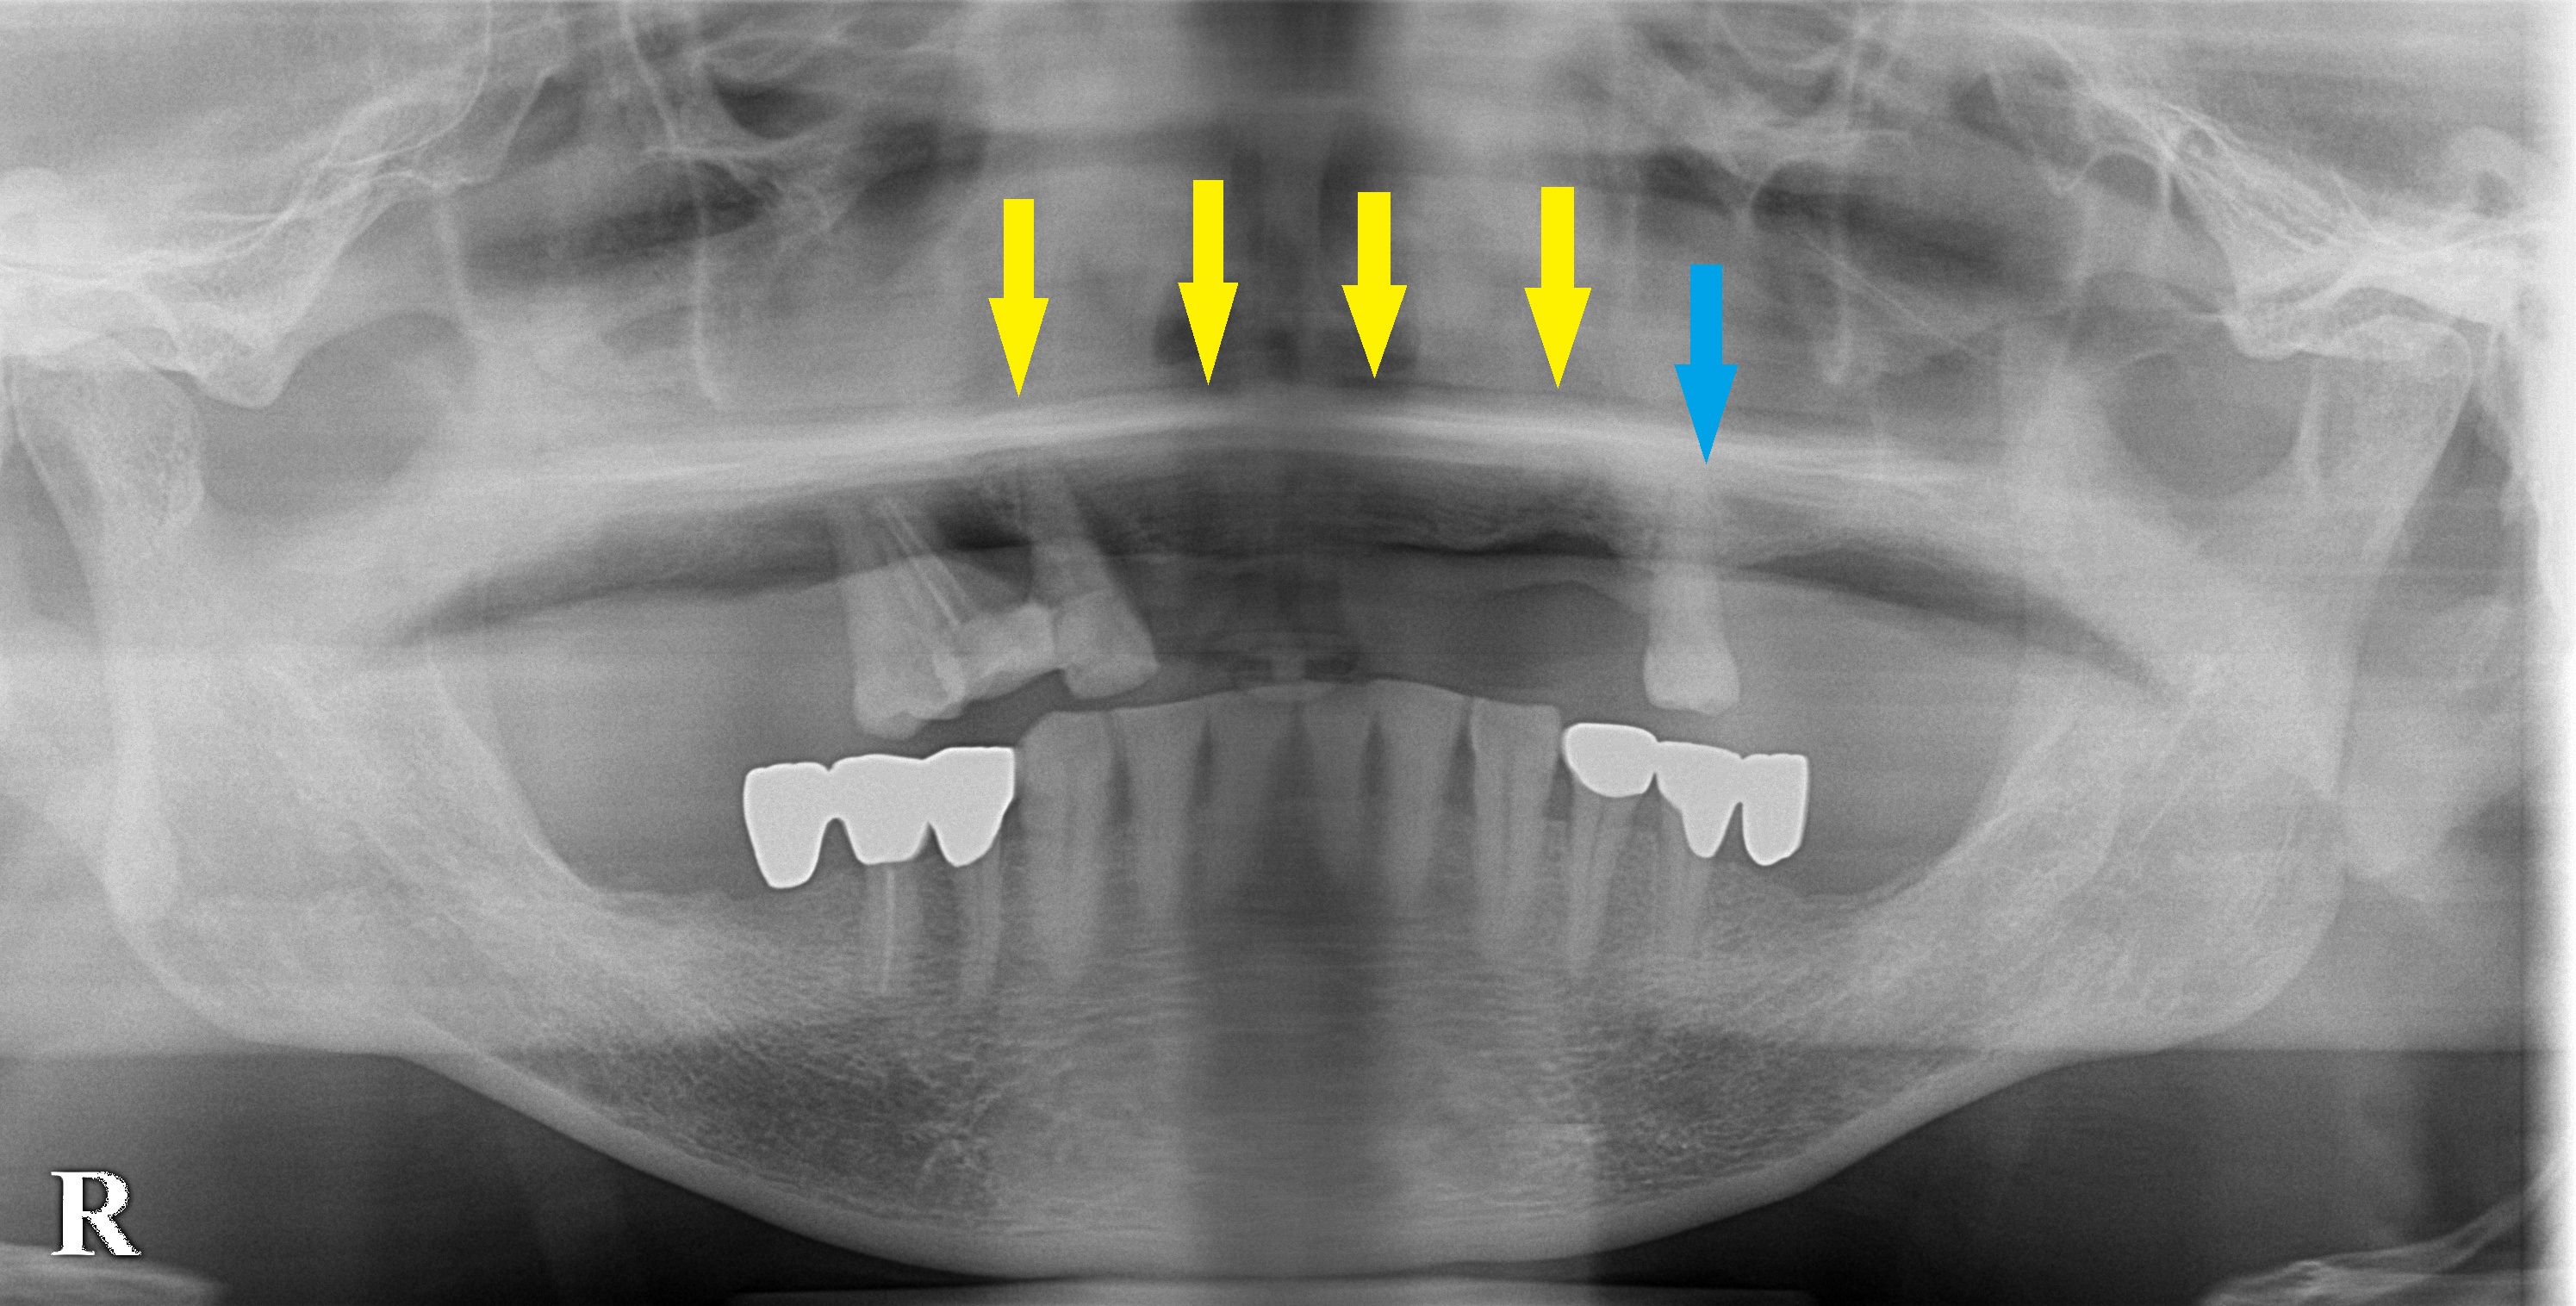

まずは下の写真の青矢印の歯のみ残して、あとは抜歯して義歯を作製しました。

検討の結果、前歯部のみに4本のインプラントを埋入して、そのインプラントに義歯の維持装置を装着して、義歯を安定させるためのインプラント治療を行うこととなりました。

本日、上顎残前歯部に、4本のインプラント埋入術を行ないました。